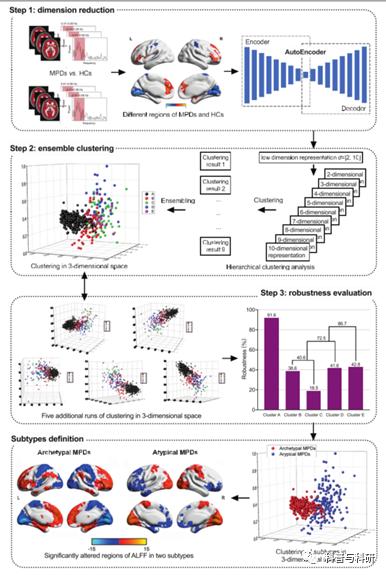

基于影像学数据的聚类分析 (理论+代码讲解+实操) |

1、聚类的基本概念 2、相似性测度 3、聚类的性能指标(Accuracy, NMI, ARI) 4、类别数目的自动确定 5、两种基本的聚类方法 1) 层次聚类 2) K-means聚类 6、结果可视化及解读 |